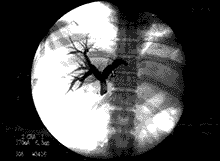

(3)胆道内支架植入术沿导丝送入胆道内支架输送器及胆道内支架,定位在狭窄段,位置确定后释放内支架,观察支架展开情况,若展开不良再用球囊导管扩张内支架使其充分展开。之后行胆道造影,观察胆道内支架是否通畅(如图1,2)。

图1 病人,女,39岁,胰腺癌梗阻性黄疸PTC示:肝内胆管扩张,肝管、胆总管闭塞

图2 胆管支架置入后,肝内胆管扩张消失,肝管、胆总管通畅,十二指肠显影。

(前头所指为支架)